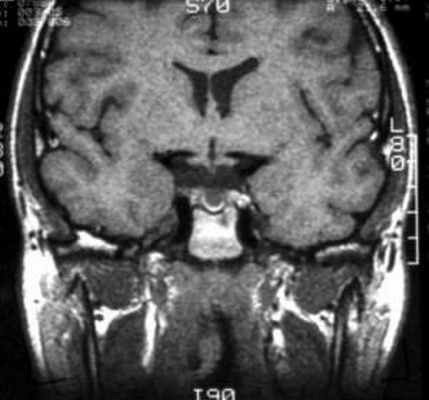

В ходе лабораторного обследования показатели общего анализа крови и мочи в пределах референсных значений, отмечено некоторое снижение протромбинового времени до 9,4 сек (10–14), повышение протромбина до 169% (70–130), общего холестерина до 5,87 ммоль/л (3,3–5,2). В гормональном анализе крови на фоне приема каберголина в дозе 0,25 мг в неделю – уровень пролактина 932,8 мЕд/л (90–540). По данным МР-томографии головного мозга в хиазмально-селлярной области подтверждено наличие объемного образования размерами 12*15*15 мм с выраженным кистозным компонентом и супраселлярным распространением (хиазма интактна). Учитывая ряд специфических признаков, специалистами отделения магнитно-резонансной томографии верифицирована киста кармана Ратке (рис. 2).

Рис. 2. Динамика объемного образования гипоталамо-гипофизарной области (А, Б – 2009 г., В, Г – 2011 г., Д, Е – 2015 г.).

На изображениях ниже можно посмотреть, как киста Ратке выглядит на снимке .

МРТ: киста кармана Ратке. На Т1-взвешенном сагиттальном изображении, полученном до введения контраста, заметно четко очерченное образование в области турецкого седла – с распространением в супраселлярную цистерну. Отмечается гомогенно высокая интенсивность сигнала в образовании по сравнению с паренхимой головного мозга.

Т2-взвешенное аксиальное изображение (тот же пациент, что и на предыдущем изображении).

Т2-взвешенное аксиальное изображение: изоинтенсивное коре образование (тот же пациент, что и на предыдущем изображении).